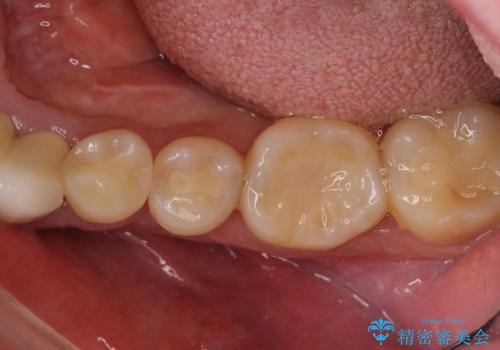

目立つ銀歯を治したい 奥歯のむし歯治療